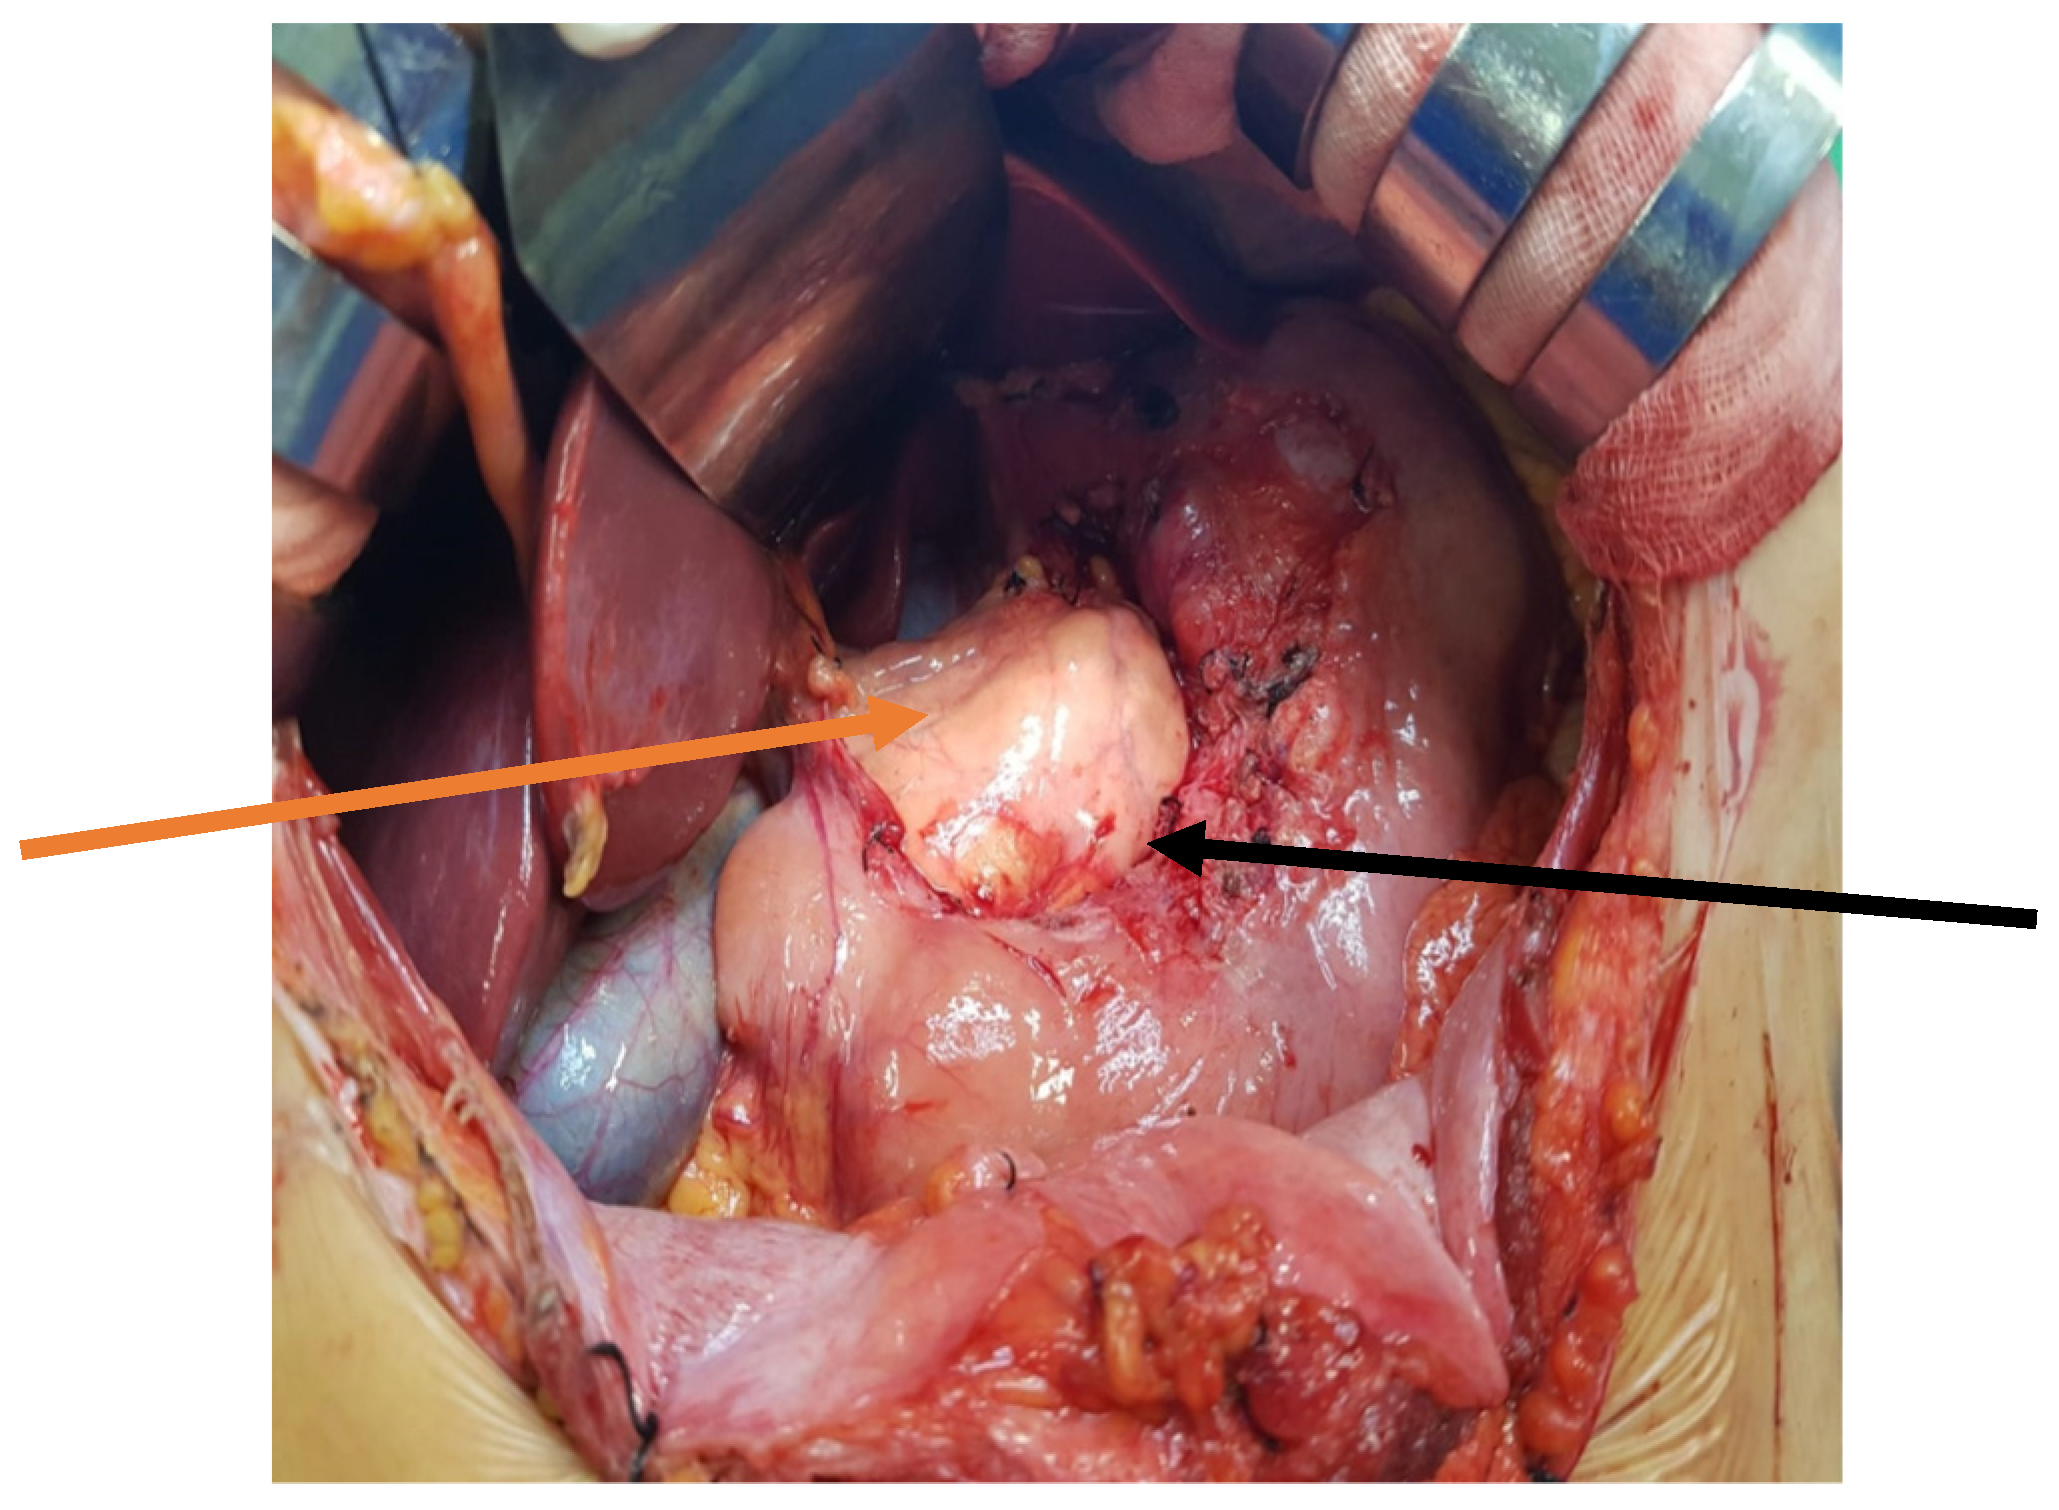

The patient was qualified for elective surgery. The presence of an approximately seven-cm long soft tissue extending along the lesser curvature of the stomach, closely connected to the stomach wall, was found intraoperatively (Figure 2). The tumour penetrated the gastrohepatic ligament, but did not reach the liver. The lesion did not penetrate the retroperitoneal space or infiltrate the pancreas. The tumour was completely removed without gastric wall resection (Figure 3). After removal of the lesion, the serosa of the lesser curvature of the stomach was secured with a continuous PDS 4/0 suture (Figure 4).

Figure 4. Intraoperative view after tumou r resection of the lesser curvature of the stomach. The arrows indicate the lesser curvature of the stomach (black arrow), and the front surface of the pancreas (orange arrow).